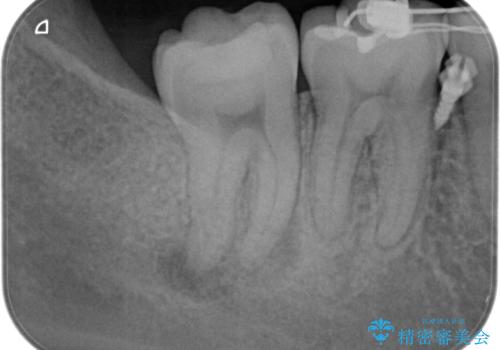

奥歯が痛い。精密根管治療〜オールセラミッククラウン

奥歯の根管治療~オールセラミッククラウン